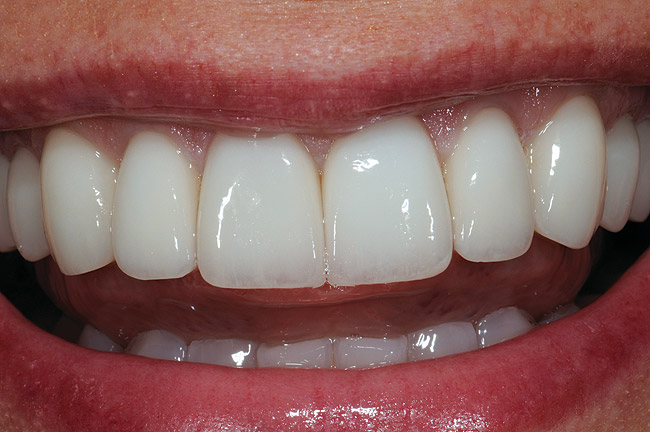

Figure 1  A magnified 1:2 view of the patient’s smile shows bilateral disharmonies as the patient smiles with medium lip dynamics.

Figure 1

A female patient presented seeking improved esthetics and full-mouth reconstruction for her smile for personal and professional reasons. A dynamic and vibrant personality with a high-profile career in the dental industry, she wanted a smile that was equally impactful. Clinically, she presented with an extensive amount of dentistry that had been done on an as-needed basis. She was conscious of the different optics resulting from the various materials used, and their contrasting appearance with one another as well as with adjacent natural teeth. Bilateral disharmonies and different clinical crown heights were evident (Figure 1).

This case illustrates the suitability of the IPS e.max layered version of crown restorations for customizing the shape and shade for this particular patient. Despite its monolithic character, the staining technique nevertheless enabled the use of one pressed color to obtain a natural look that blended in well with natural adjacent teeth (Figure 18). Proper ingot selection and precise knowledge of what tooth structure was being worked on to ensure exact color blending with the tooth’s substructure was instrumental in the successful outcome. The patient, whose career often requires on-stage appearances, was highly pleased with the outcome—a healthy, natural- and youthful-looking, bright smile that “popped” and exuded powerful confidence (Figure 19 and Figure 20).